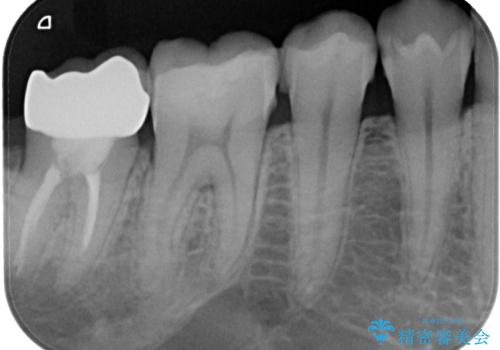

- 右下の奥歯が大きく欠けてしまったのを治したいと来院された患者様です。

舌側の歯冠がなくなってしまっていて、健全な歯質が歯茎の下にある状態です。

このままの状態だと土台がたてられず被せものがいれられないため、歯肉の切除と歯槽骨の形態修正を行い、歯の健全な部分が歯肉の外に出てくるようにしたうえで、オールセラミッククラウンによる補綴治療を行うこととしました。

根管治療のやり替えも提案しましたが、希望されなかったため行いませんでした。